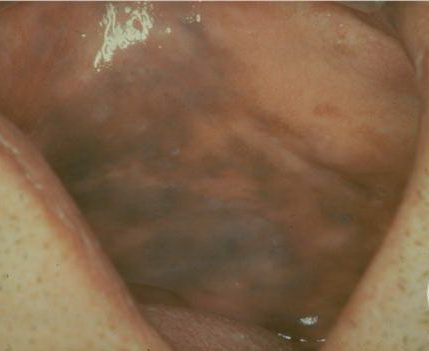

Mucosal Lentigines = النمش على الغشاء المخاطي